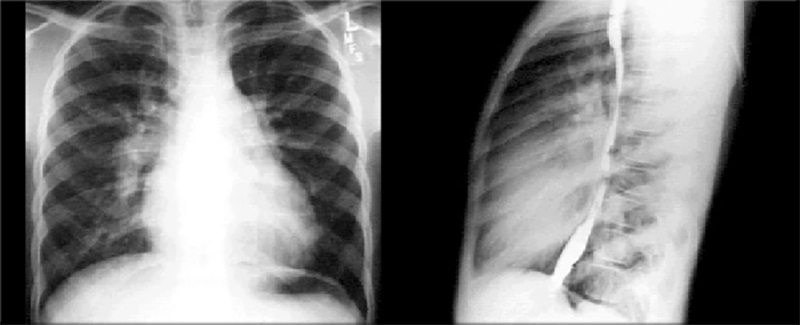

These chest X rays show right ventricular enlargement, a dilated pulmonary trunk and increased pulmonary arterial vascularity.

Right ventricular enlargement is suggested in the PA view by the upturned apex and the minimally increased cardiothoracic ratio.

It is suggested in the lateral view by obliteration of the retrosternal air space.

The PA view shows dilation of the pulmonary trunk, manifested by the convex density below the aortic knob.

Both views show prominence of the pulmonary artery, particularly well seen in the PA view as dilation of the right pulmonary artery.

Increased pulmonary arterial vascularity is reflected further by prominent distal arterial markings. These chest X rays are consistent with a large atrial level left-to-right shunt, as in an atrial septal defect.